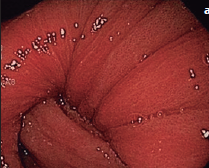

Imágenes y Cirugía

Natalia González Alcolea, María Dolores Chaparro Cabezas, Félix Martínez Arrieta, Victor Sánchez Turrión